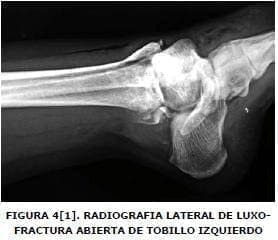

Se realizan radiografías y se hace diagnostico de fractura en articulación sacro ilíaca bilateral con subluxación del anillo pélvico superior de predominio izquierdo (Figura Nº 1), luxofractura de Lisfranc derecha (Figuras Nº 2 y 3), y luxofractura abierta tobillo izquierdo (Figura Nº4).

Al examen físico de ingreso presentó: frecuencia cardiaca de 96 latidos por minuto, 20 respiraciones por minuto, tensión arterial 80/60 mm/hg. Se encuentra herida de trescentímetros en maléolo peroneal izquierdo con exposición de maléolo, sangrado escaso, edema y deformidad en tobillo y pie derecho, dolor a la palpación en alerón iliaco izquierdo.

Se aplicó antibioticoterapia biconjugada y manejo de tejidos blandos. Quince días más tarde, se realizó reducción abierta con osteosíntesis definitiva con clavos de Kirschner en luxofractura de pie derecho tipo Lisfranc B2, con desplazamiento lateral. Encontrándose minutas en los metatarsianos (Figuras Nº 5 y Nº 6), en tobillo izquierdo se adelantó reducción abierta mas osteosíntesis con tornillos de esponjosa en superficie articular anterior de tibia distal y con clavo de Steinman se fijó articulación tibioastragalocalcanea, izquierda (Figura Nº 7). La paciente presento escaras sacras con evolución favorable y finalmente salió de alta hospitalaria a los 64 días de ocurrido el trauma.

Se aplicó antibioticoterapia biconjugada y manejo de tejidos blandos. Quince días más tarde, se realizó reducción abierta con osteosíntesis definitiva con clavos de Kirschner en luxofractura de pie derecho tipo Lisfranc B2, con desplazamiento lateral, encontrándose minutas en los metatarsianos (Figuras Nº 5 y Nº 6), en tobillo izquierdo se adelantó reducción abierta mas osteosíntesis con tornillos de esponjosa en superficie articular anterior de tibia distal y con clavo de Steinman se fijó articulación tibioastragalocalcanea, izquierda (Figura Nº 7).